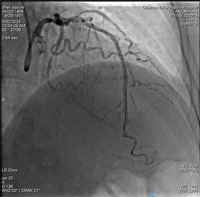

8个月前因心绞痛入院冠脉造影检查,提示前降支中段、远段均有严重狭窄,当时远段病变普通球囊及切割球囊均不能扩张,只予中段病变处植入一枚支架。本次患者胸闷、胸痛考虑犯罪血管为前降支远段病变,IVUS检查可见>270°钙化环,本次直接给患者使用国内最新的冲击波球囊,采用血管内冲击波治疗。选择一枚2.5mm*12mm冲击波球囊分别送至前降支远段钙化部位,总共发放3组冲击波,冲击波结束后,造影可见钙化部位狭窄明显减轻,经IVUS检查可见钙化环多处断裂,随后由远至中段原支架远端串联植入2枚支架。整个手术过程中,患者无任何不适症状。